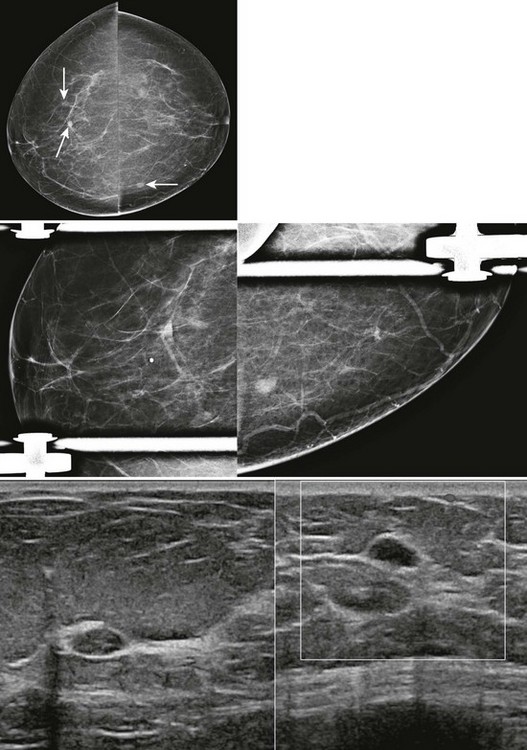

FIGURE 8-4 Metastatic Lesions in the Breasts.

This 47-year-old woman presented with a palpable lump in the right breast (marker). There are multiple circumscribed masses in both breasts. Note that the masses are primarily located in the retromammary fat and even in the axillary fat. US shows a solid hypoechoic mass with microloculated margins. Ultrasound-guided core biopsy samples were black in appearance. The patient subsequently gave a history of ocular melanoma 5 years earlier. Biopsy showed metastatic melanoma.